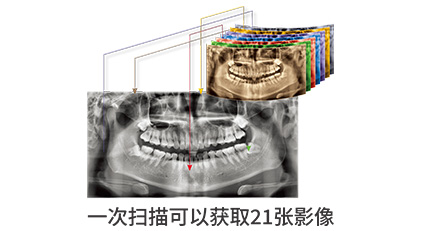

多功能全景

多功能全景是第三代全景技术,其核心是通过提供多个层面深度解析。它可以使以前看不清楚的区域更加清晰。它获取多层图像并自动结合,以提供全景图像的深度信息。每个病人都有不同类型的牙弓。对于磨牙区存在多根管的情况,传统的全景只能查看一个层面上的图像,很难得到准确的信息。现在提供多层次,并增加了全景图像的深度,让其获得更多的影像信息。